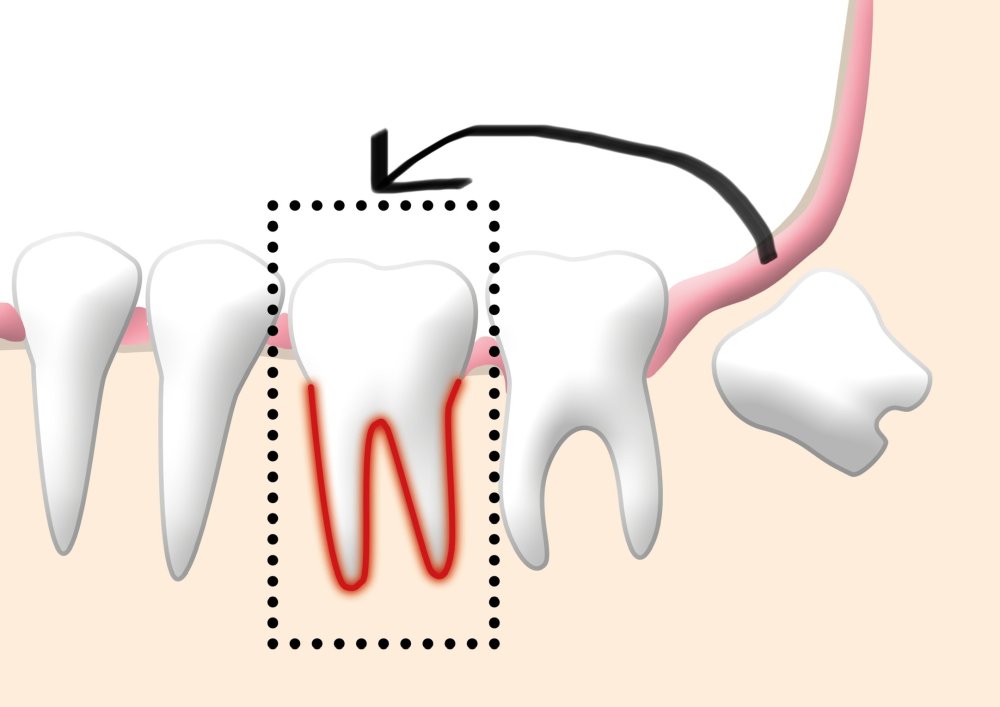

Diş autotransplantasiya, diş həkimliyi sahəsində geniş yayılmış bir cərrahi prosedurdur. Bu prosedur, bir dişin bir bölgədən götürülüb başqa bir bölgəyə yerləşdirilməsini əhatə edir. Əsasən, çürük, travma və ya digər səbəblərlə itirilmiş bir dişin yenisi ilə əvəz edilməsi məqsədilə tətbiq olunur. Autotransplantasiya zamanı uğurlu nəticə əldə etmək üçün adətən köçürüləcək dişlərdə köklərin tam formalaşmamış olmasına diqqət yetirilir. Bu baxımdan bu müalicə metodu daha çox uşaqlarda və gənclərdə daha çox uğurla tətbiq edilir.